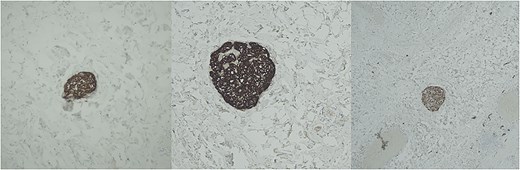

Histopathological analysis of the gallbladder demonstrated follicular cholecystitis along with an incidental paraganglioma (Fig. 4). This lesion showed positivity with CD56, synaptophysin, and chromogranin staining with admixed S100-positive sustentacular cells (Fig. 5). Keratin was negative.

Gallbladder paraganglioma with characteristic Zellballen pattern seen in hematoxylin and eosin, ×20.